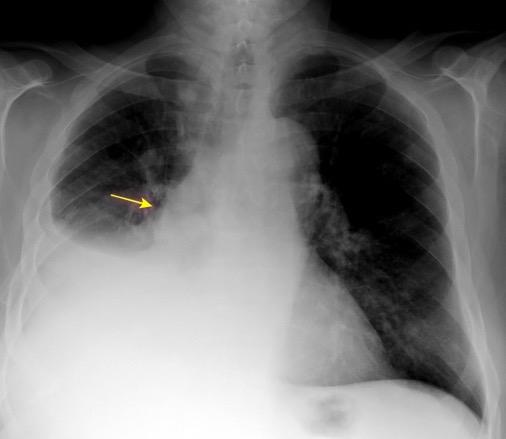

Triada de Garland

Ganglios paratraqueales derechos e hiliares bilaterales

95% de pacientes tienen ganglios hiliares bilaterales aislados o con afectación mediastínica (espec. paratraqueal derecho).

Criado E et al. Pulmonary sarcoidosis: typical and atypical manifestations at high-resolution CT with pathologic correlation. Radiographics. 2010